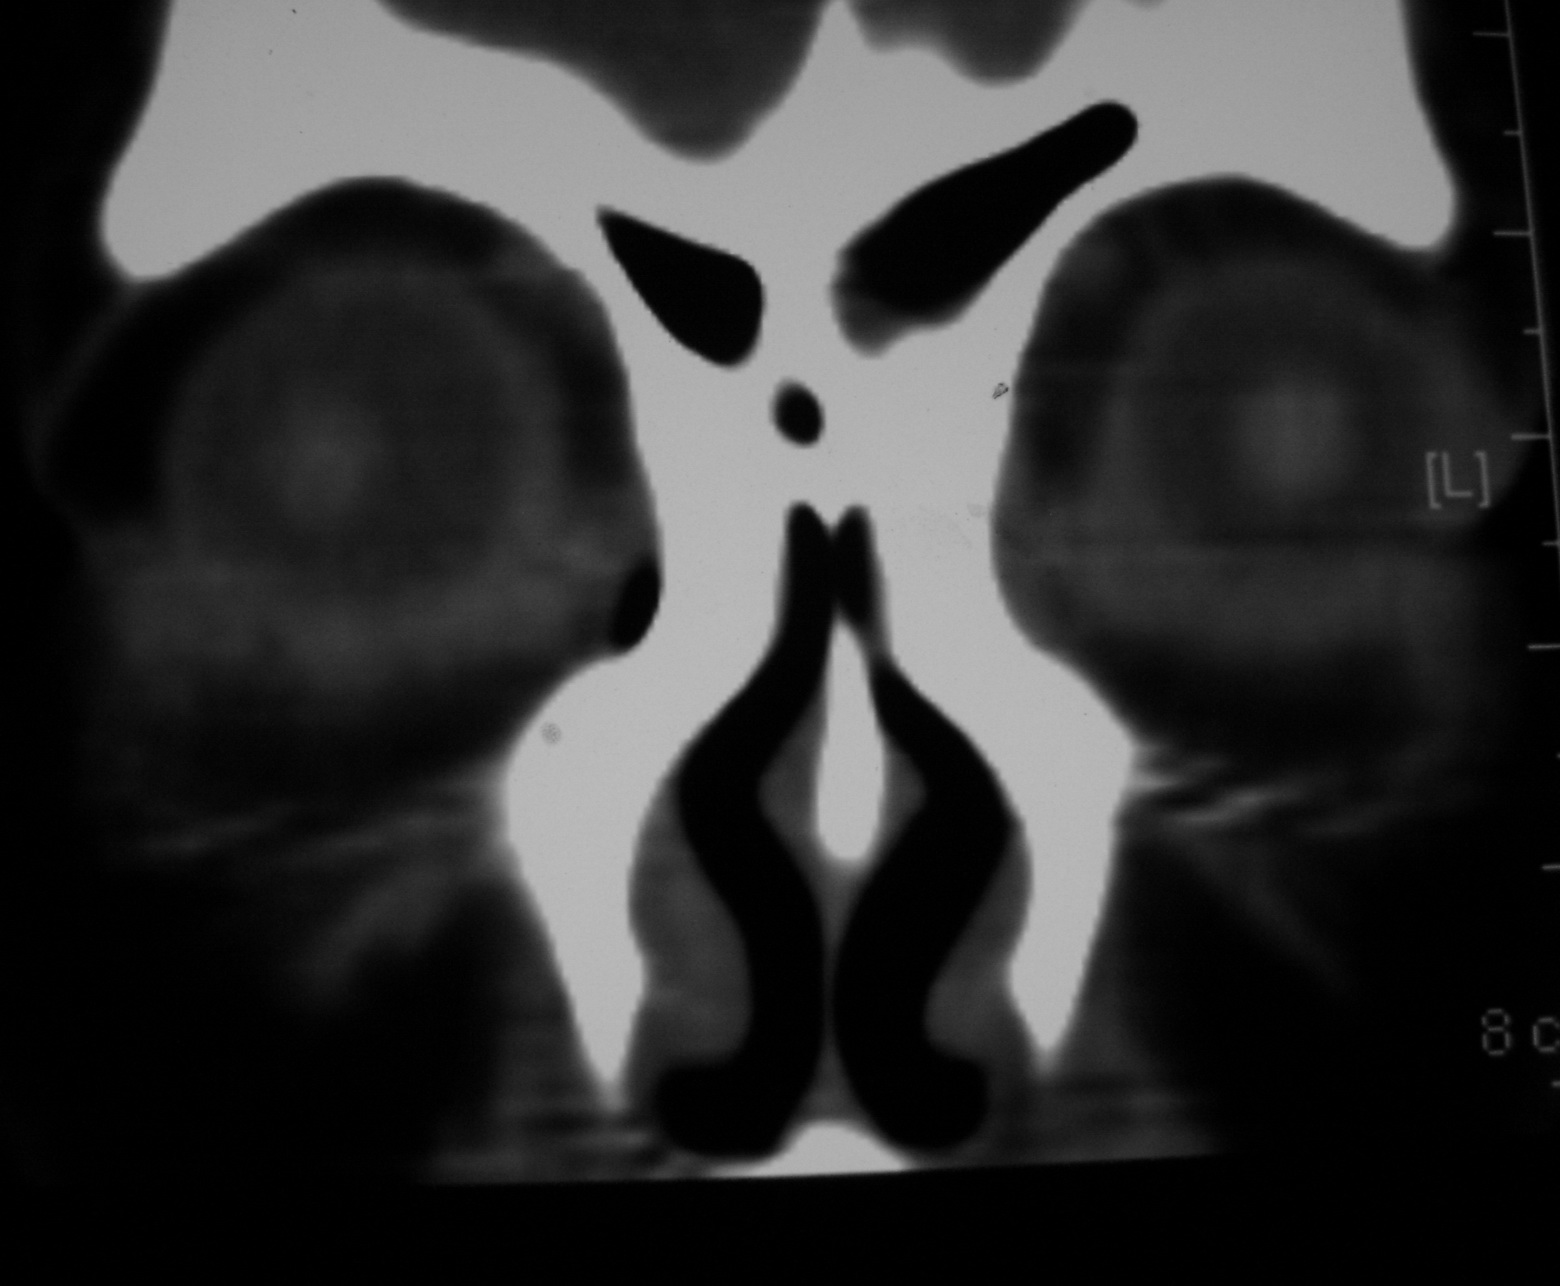

右侧眼眶脂肪瘤

女,34岁。右眼不适半年。

会员诊断:

表皮样囊肿、皮样囊肿、脂肪瘤

手术病理

:右侧眼眶

脂肪瘤

。